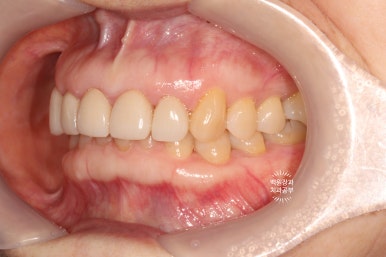

옆에서 보아도 너~무 잘 보이는 앞니 세로 금. 치아의 끝단에는 충치로 생각되는 어둑함이 자리잡고 있었고..

사진을 보시면 아시겠지만, 오른쪽 위 어금니 두개가 없으신 상태였습니다.

좌측과 우측 측면에서 보아도 아주 깔끔하게 유지되고 있는 앞니 지르코니아 크라운들입니다.

매우 흡족한 결과입니다 :)